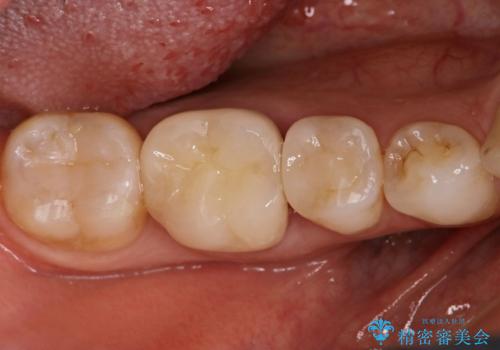

- 銀歯が気になるためやり替えたいとのことで来院されました。

セラミックインレーで治療を行いました。

口の中にチラつく銀歯は適合の良いセラミックインレーでやり替えることで綺麗にやり替えることができます。